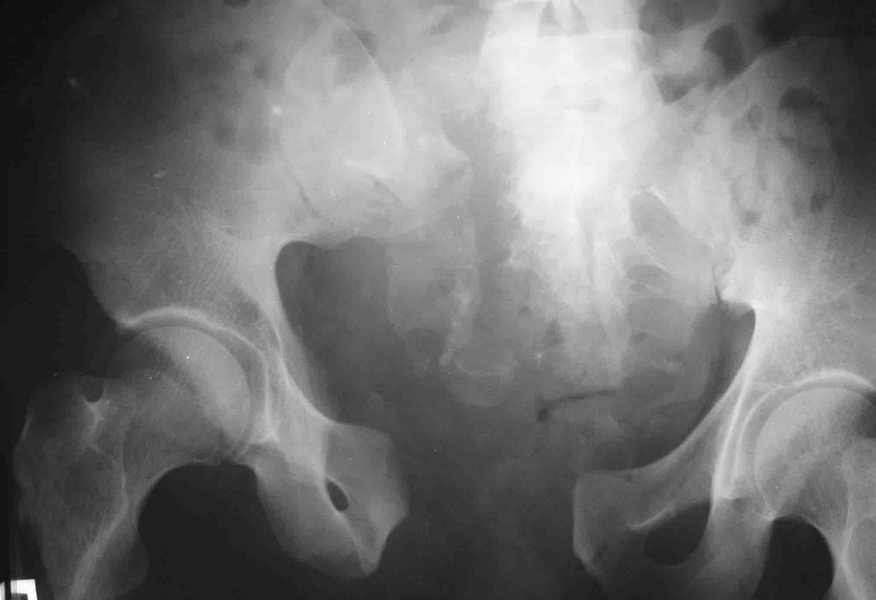

Вот вариант решения похожей ситуации